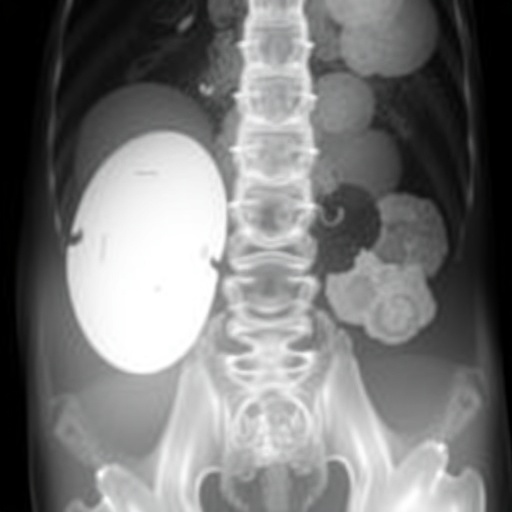

The subject of the case was a multiparous woman who presented with non-specific complaints, including persistent lower abdominal and back pain, alongside her initial episode of prolonged menstrual bleeding—symptoms that initially appeared unrelated to vulvar pathology. Clinical examination revealed a large, soft, pedunculated mass on the left labia majora. The lesion’s appearance closely mimicked a lipoma, a benign fatty tumor commonly encountered in soft tissue diagnoses. Additionally, smaller cystic lesions were noted bilaterally on the inner labia minora, clinically consistent with Bartholin gland cysts. This concurrent presentation inadvertently complicated the clinical picture.

Subsequent surgical excision of all identified lesions provided the means for comprehensive histopathological evaluation. The large mass was confirmed as a mucinous cyst, characterized by a lining of mucinous columnar epithelium devoid of malignant features. The smaller inner labial cysts were histologically consistent with Bartholin gland cysts. This dual pathology within the same anatomical region in a reproductive-age woman is exceptionally unusual and has significant implications for differential diagnoses in gynecologic practice.